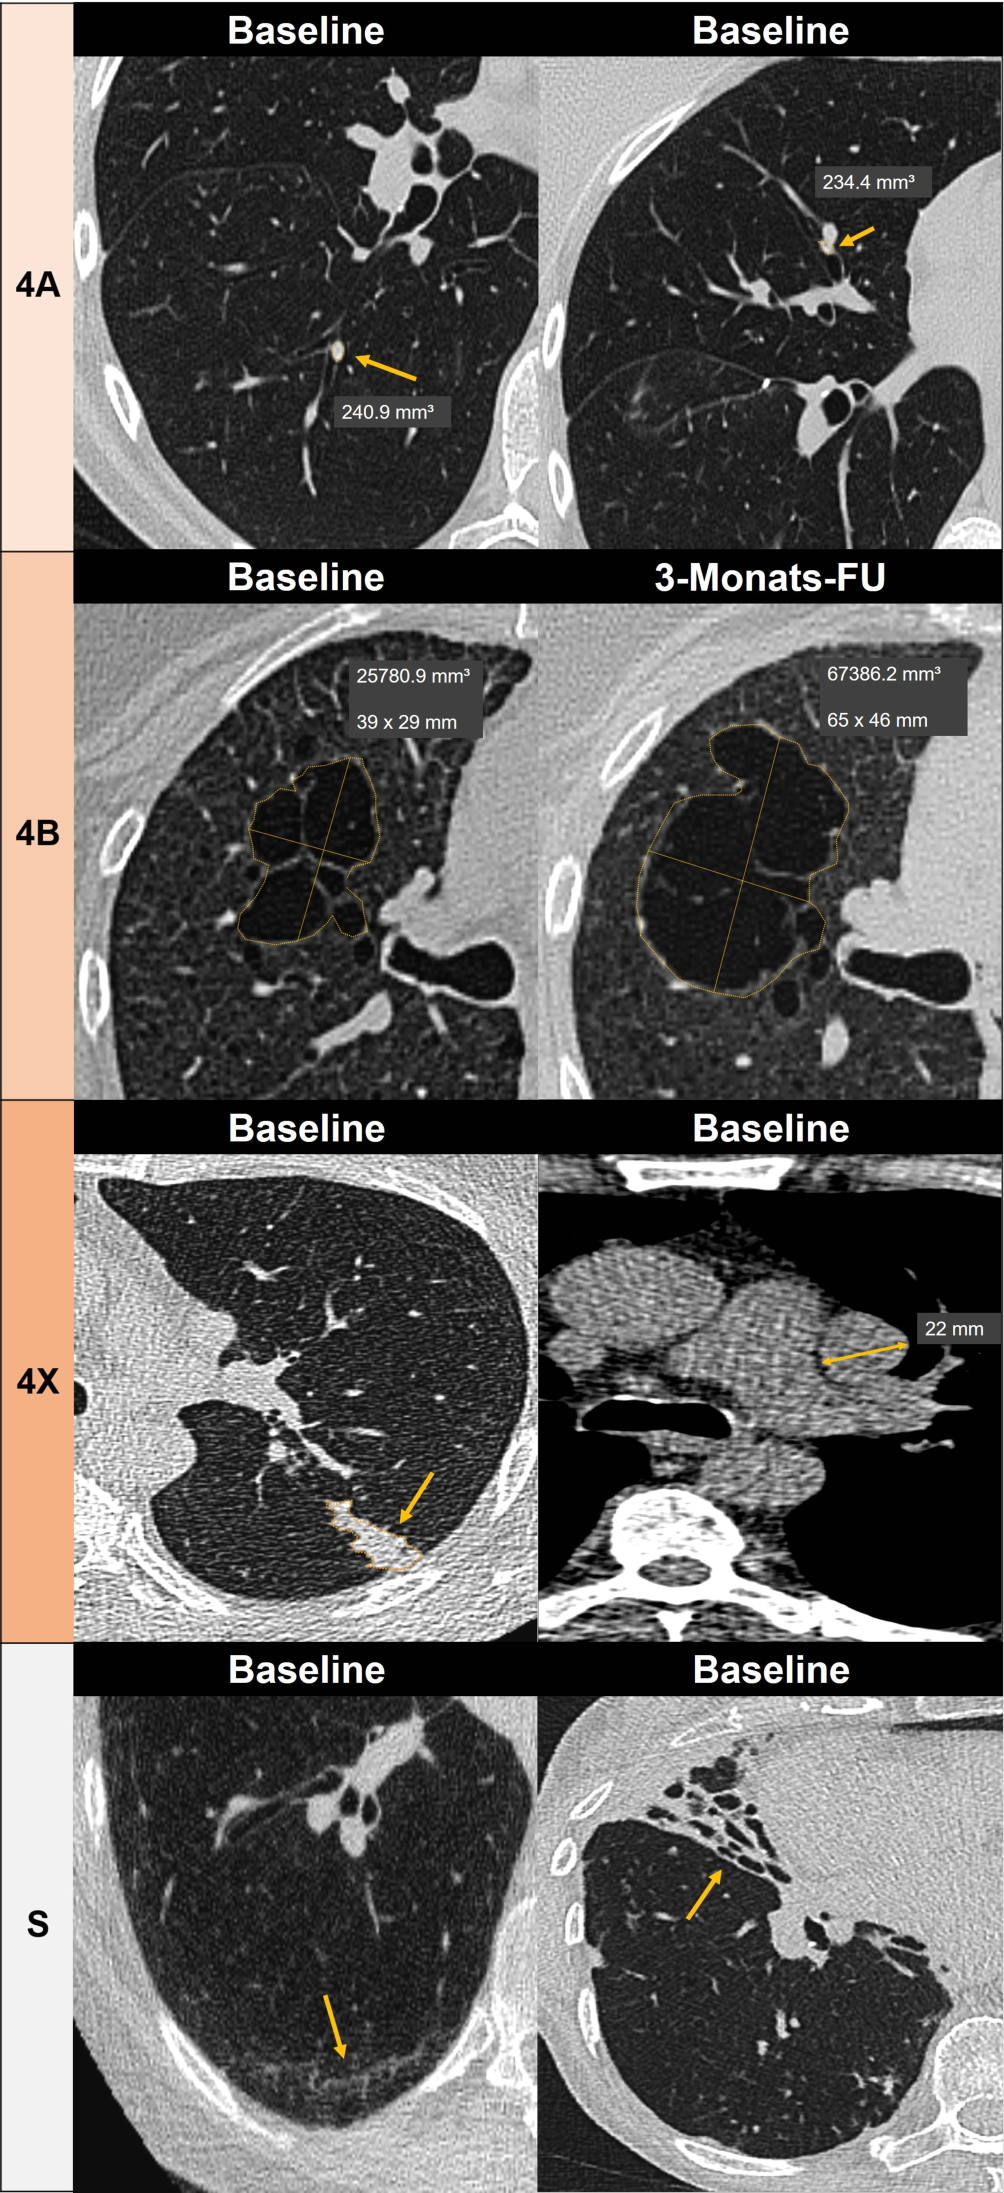

Abb. 1

Beispiele für Lungenläsionen unter Anwendung von Lung-CAD-Software mit Klassifikation gemäß Lung-RADS: 4A Solide endobronchiale Rundherde segmental im rechten Unterlappen (links) und Mittellappen (rechts) in der Baseline-LDCT, histologisch: typisches Karzinoid. 4B Multilokuläre Zyste mit deutlicher Größenzunahme und vermehrter Septierung in der 3‑Monats-Follow-up-LDCT, histologisch: adenoid-zystisches Lungenkarzinom. 4X Segmentale Obstruktion eines linken Oberlappenbronchus mit ipsilateraler mediastinaler Lymphadenopathie, histologisch: kleinzellig neuroendokrines Karzinom, Stadium T2aN2M0. Modifier S (Klinisch relevante Befunde ohne Hinweis auf Lungenkrebs). Links Interstitielle Lungenanomalien (ILA), Rechts Bronchiektasen